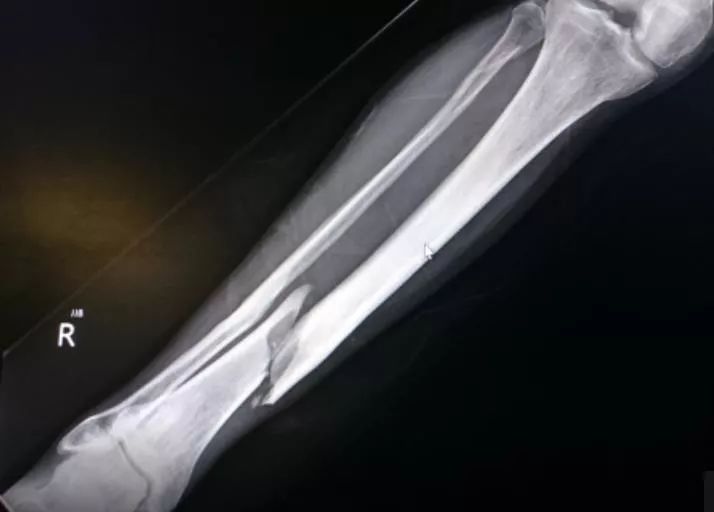

2、骨折的处理:

骨折的分辨:

外伤后出现畸形,可确诊;

外伤后剧烈而持久的疼痛,高度可疑。

下肢骨折的处理:

夹板固定,至少为单夹板,推荐双夹板。

注:“夹板”仅为概念,户外时可就地取材用树枝等,不可过短。

绑定要牢固,脚踝等皮肤较薄处需垫些衣物等用以保护。

搬运时注意受力点,避免对患肢进行牵拉。